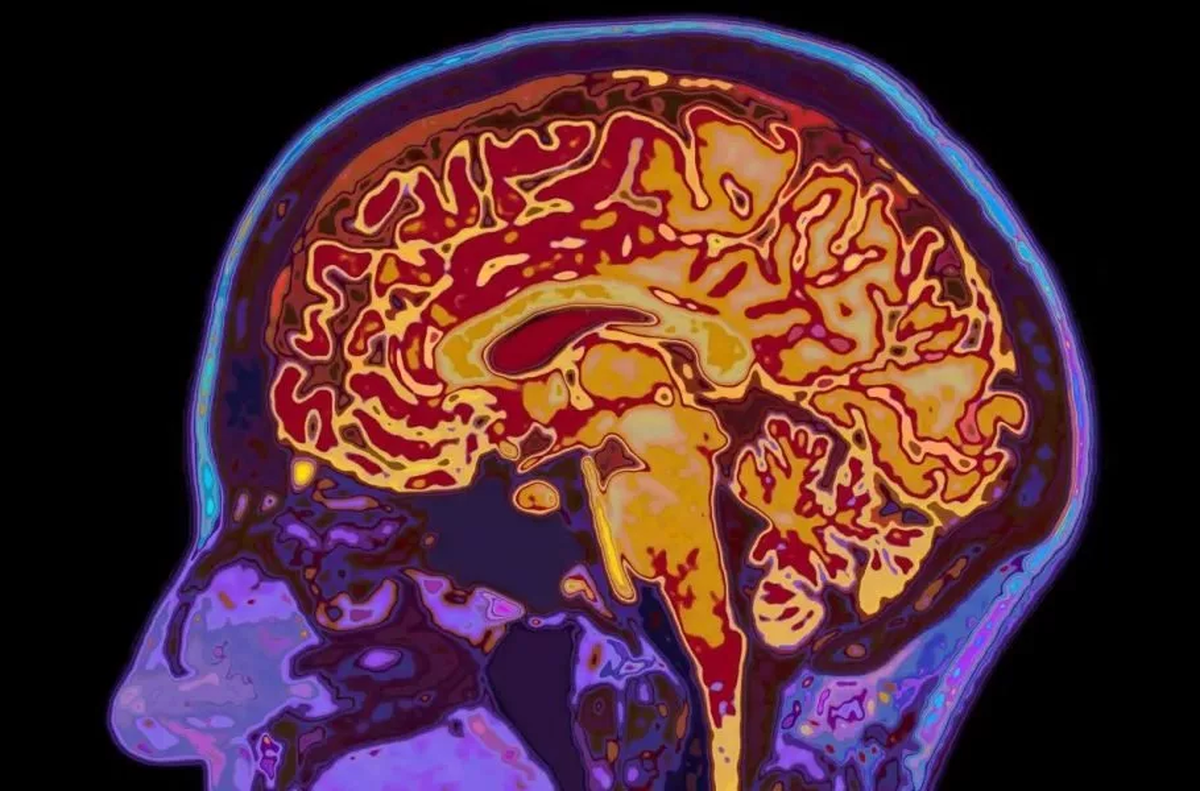

شوک علمی: مغز انسان تا ۳۲ سالگی کامل نمیشود

دانشمندان دریافتند مغز انسان ۵ دوران رشد دارد که نوجوانی آن تا ۳۲ سالگی ادامه مییابد.

شاید فکر کنید با تمامشدن دوران نوجوانی، مغز شما هم به بلوغ و رشد نهایی رسیده است. اما دانشمندان دانشگاه کمبریج این باور قدیمی را رد کردهاند. آنها با اسکن مغز ۴ هزار نفر (از نوزاد تا ۹۰ ساله) کشف کردند که مغز انسان نه یک مسیر خطی، بلکه ۵ دوران متمایز را طی میکند. محققان میگویند مغز ما تازه در اوایل دهه ۳۰ زندگی وارد فاز بزرگسالی میشود.